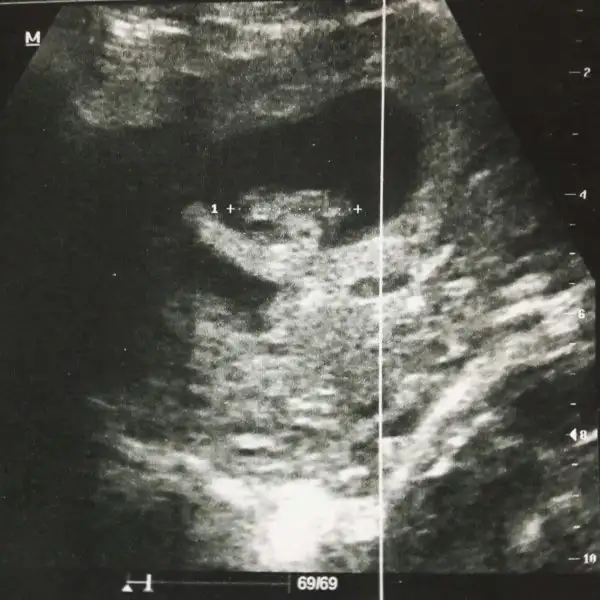

Bu da benim minis .. bakalım bende öğrenince yazarım..

Ay inşallah ya.. Bir kızım var zatencanım senin erkek gibi yaaaaaa valla umutlandırmakta istemiyom ama ne bilim içimden hep öle geçiyo teoriler vs de onu gösteriyo zaten.